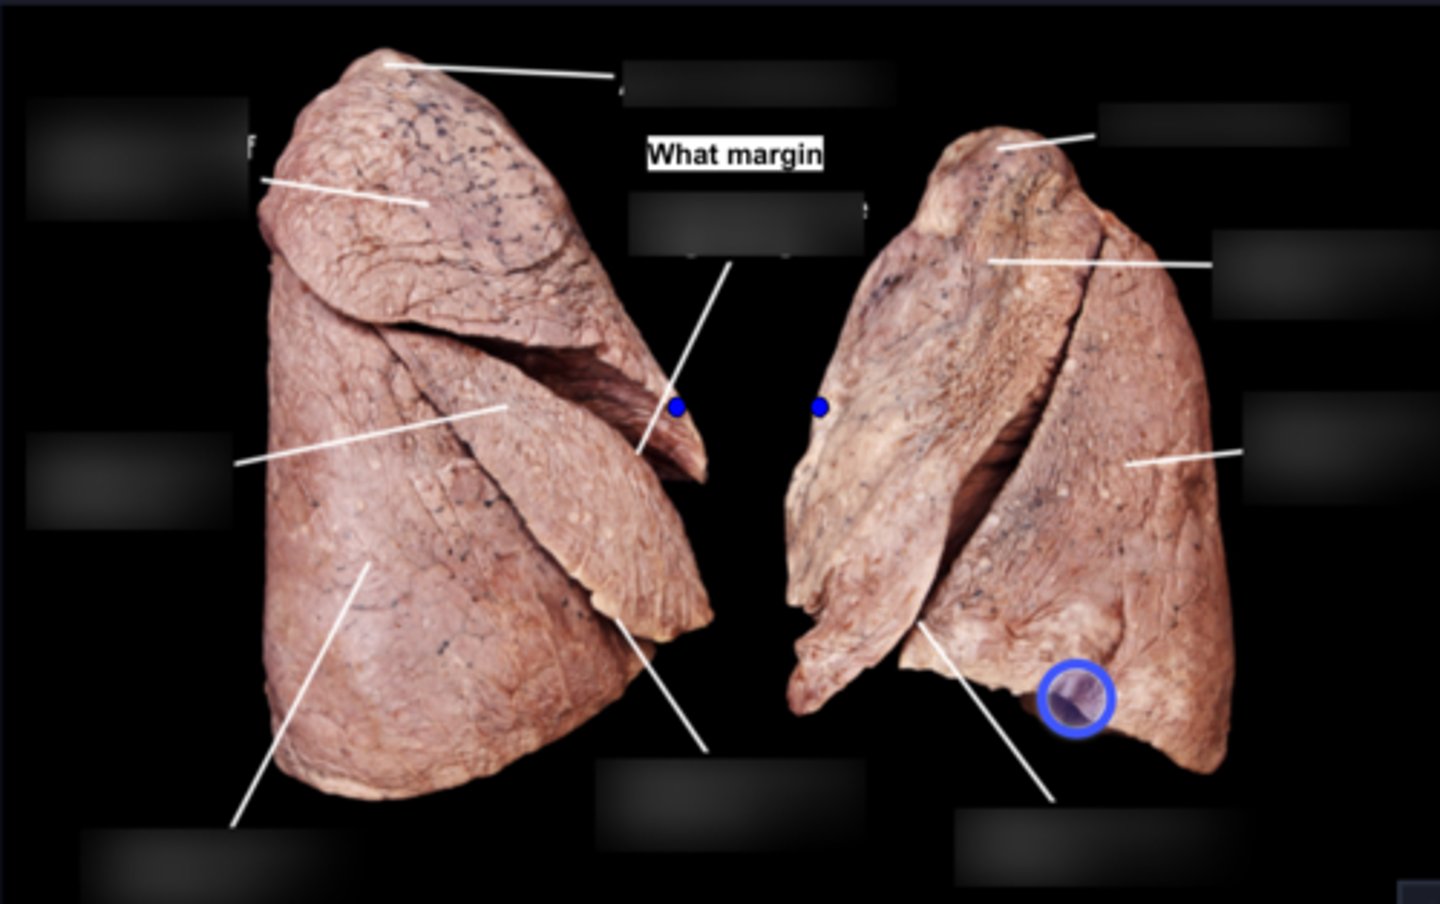

Superior lobe of right lung

Middle lobe of right lung

Inferior lobe of right lung

Superior lobe of left lung

Inferior lobe of left lung

Lingula

Apex

Base/Diaphragmatic Surface

Costal Surface

Mediastinal Surface

Anterior Margin

Posterior Margin

Visceral Plurae